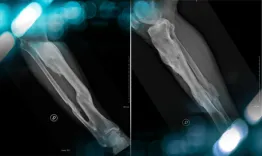

The goals of this clinical case are to discuss the periprostetic femoral fractures and their treatments

Management of a peri prostetic femoral fracture

Vincent Marot